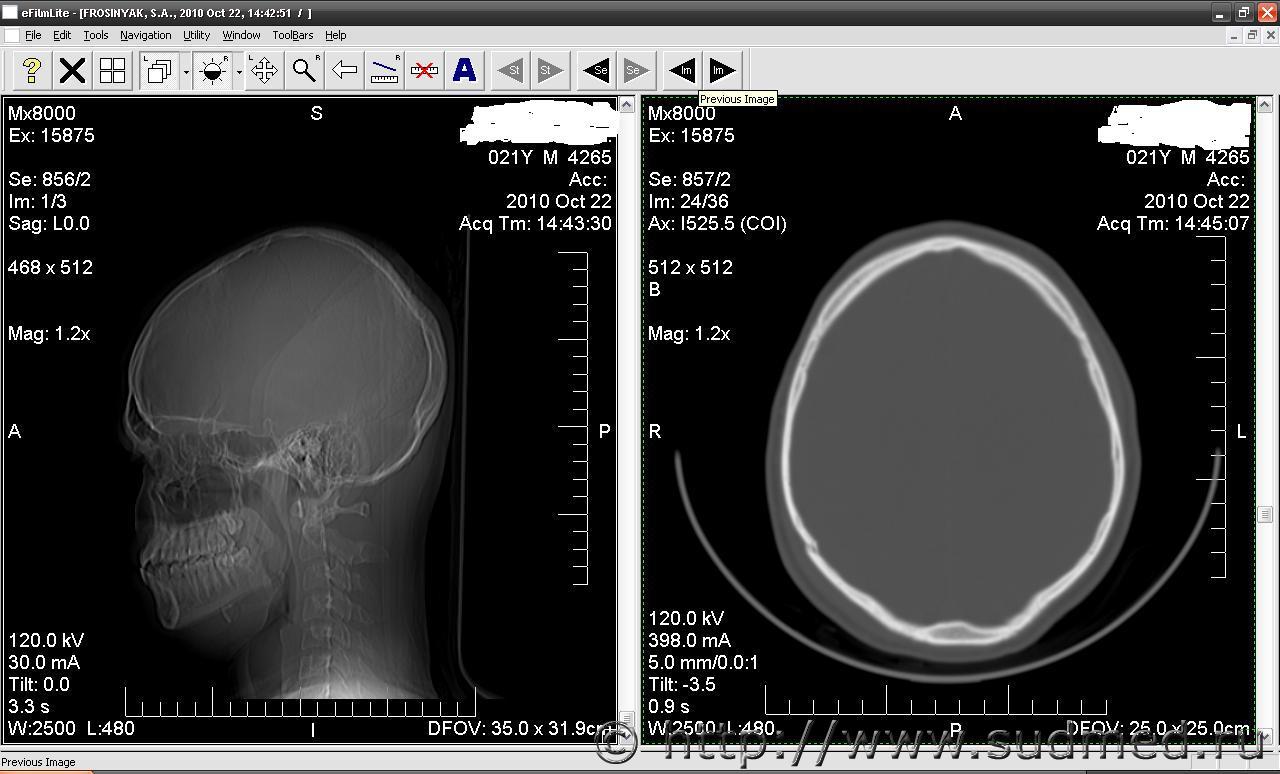

Уважаемые Експерты нужна Ваша консультация. Обстоятельства дела: человек получает несколько ударов молотком по голове в теменую и затылочною область. Находился на стац.лечении ДЗ: перелом костей затылочно-теменой области, ушиб головного мозга 1-2 ст. Согласно КТ заключения один рентгенолог указывает на перелом темено-затылочной области. Другой рентгенолог на (снимки теже) указывает на костные изменения без указания на травматический характер. В обследуваемого рание согласно меддокументов травм головы не было. Вопрос, имеются ли на предоставленых снимках костно-травматические или другие изминения. прошу прощения немогу прикрепить снимки, подскажите как ?

Перелом виден хорошо, действительно где-то на границе теменной и затылочной костей.

Часть перелома линейная, скошена, часть с отрывом внутренней костной пластинки.

Чего там мудрить?